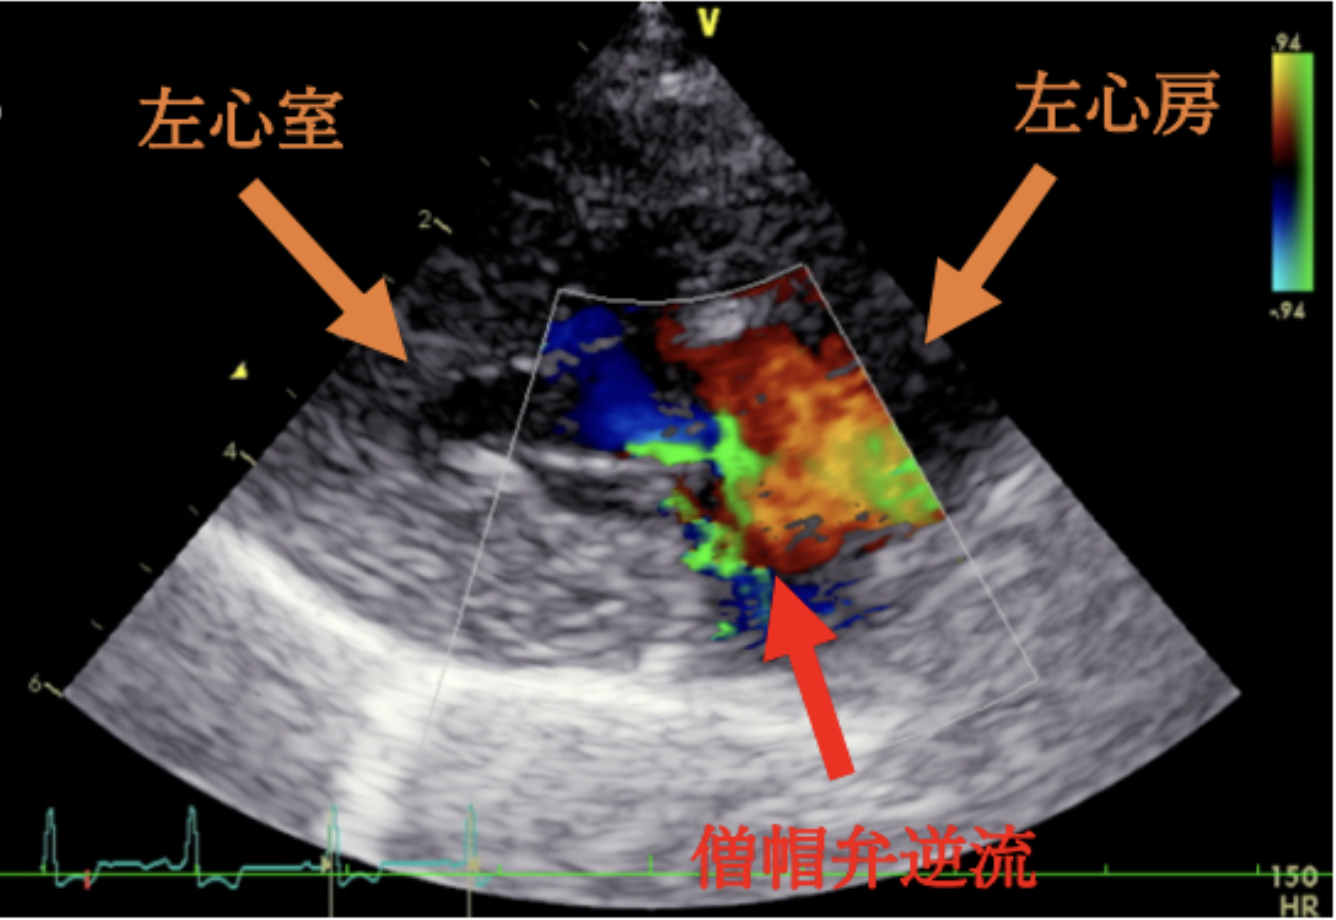

<症例情報>雑種⽝ 16歳 8か⽉齢去勢済みの男の⼦、⼼雑⾳を認める 主訴:ふらつきがある <心臓超音波検査結果> …